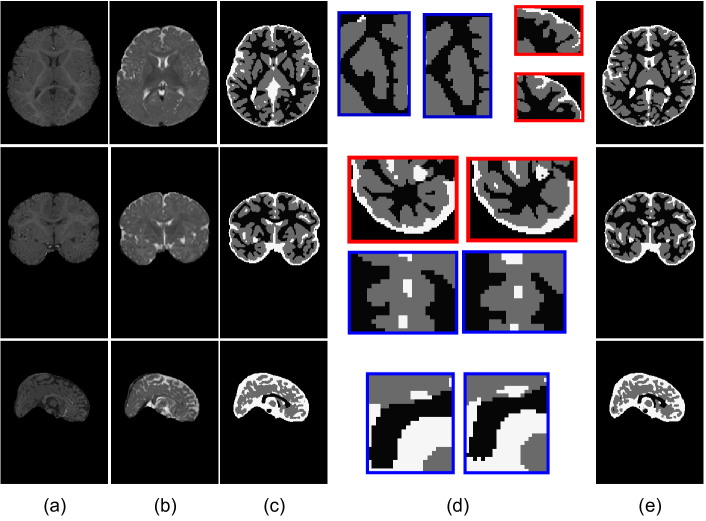

Refer to caption

Figure 3: Visualization of validation subject i.e. subject #9. (a) and (b) are T1- and T2-weighted brain MRI scans of subject #9 in different views. (c): predicted segmentation results by our 3D ConvCaps; (d) Enlarged view of some random regions between (c) and (e). Blue boxes indicate some spots produced correctly by 3D ConvCaps. Some regions where 3D ConvCaps yielded incorrect segmentations are outlined in red ; (e): ground truth. Top-down: visualize in different planes: axial, coronal, and sagittal.

The qualitative evaluation of 3DConvCaps on iSeg is shown in Fig. 3 on validation subject, i.e subject #9.